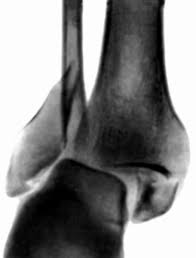

ПЕРЕЛОМ ЯКОЇ КІСТКИ І ЯКОЇ ЇЇ ЧАСТИНИ ВИ БАЧИТЕ НА РИСУНКУ?

варіанти відповідей

ДИСТАЛЬНОГО ДІАФІЗА

HUMERUS

ULNA

RADIUS

ПРОКСИМАЛЬНОГО ЕПІФІЗА

ДИСТАЛЬНОГО ЕПІФІЗА

ДІАФІЗА

МЕТАФІЗА